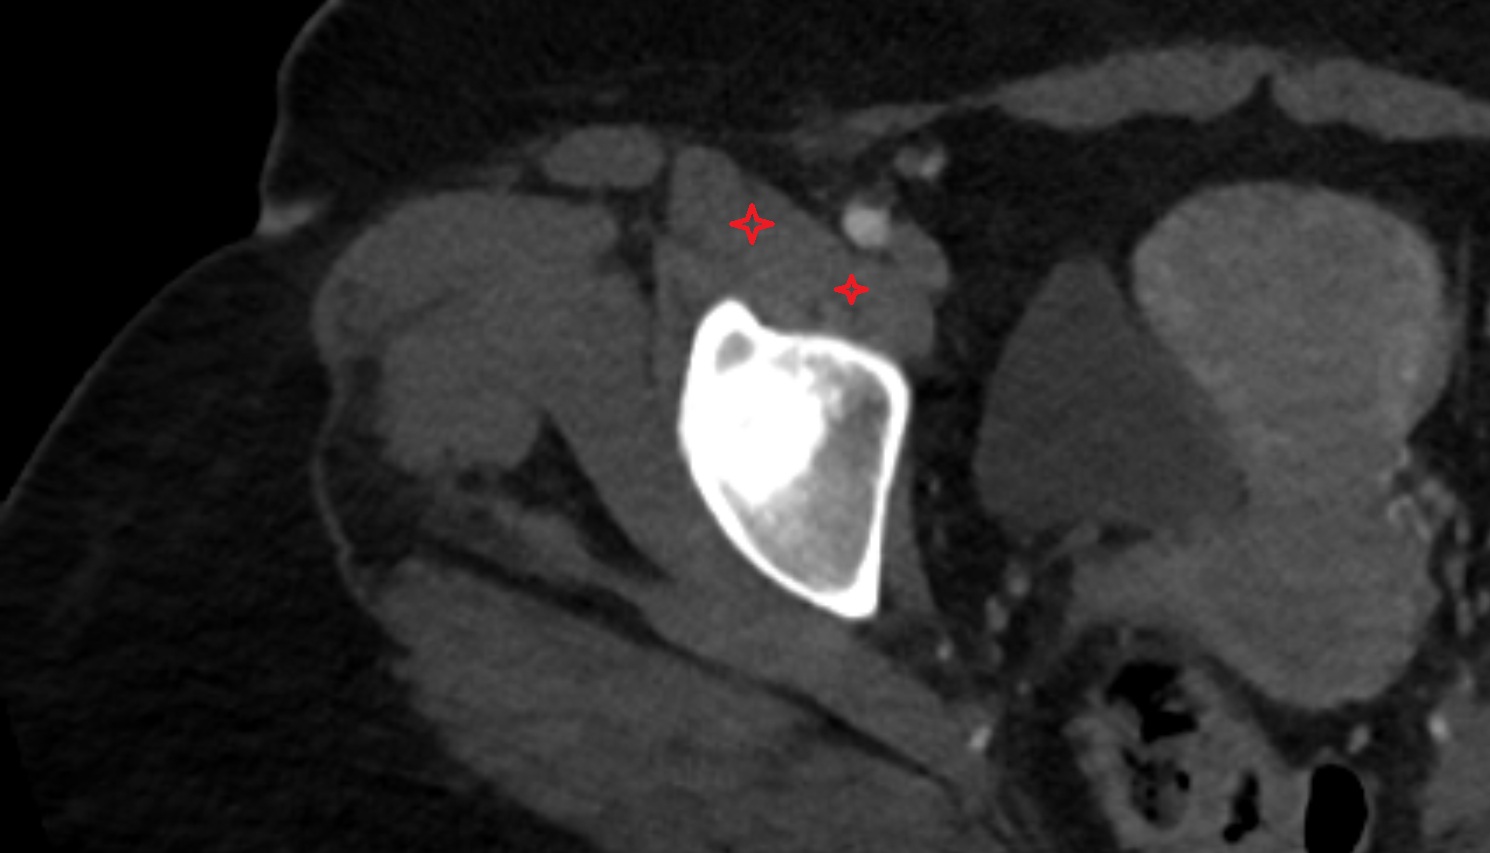

- Subacromial space